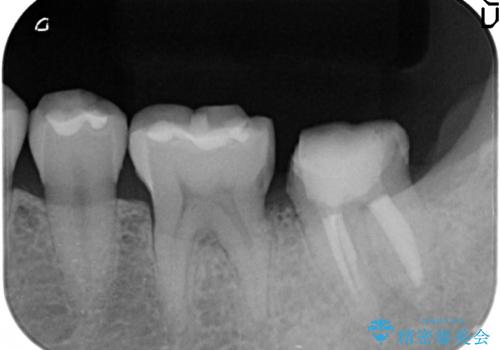

- 左下の一番奥の歯が時折激しく痛むので診て欲しいといらっしゃった方の症例です。以前に他院を受診したところ、そもそも被せ物を入れるスペースがないため抜歯しかないと言われたとのことでした。

診査の結果根尖病変を認めたため再根管治療を行った後に、被せ物を入れるスペースを作るため歯冠延長術を行いました。